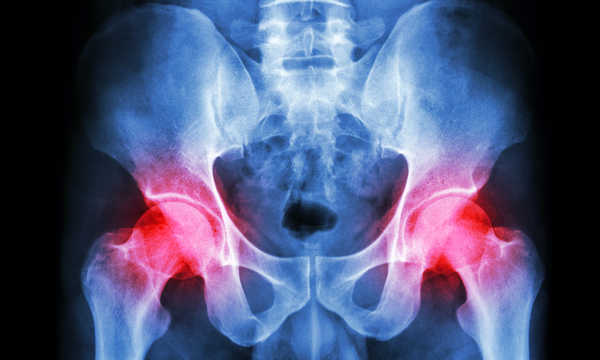

Zwyrodnienia stawów biodrowych to najczęstsze problemy układu ruchu, z jakimi zmagają się ludzie starsi i w średnim wieku oraz osoby mało aktywne fizycznie. Jedną z tego typu chorób jest chondropatia, niszcząca chrząstkę otaczającą kości stawów, wywołująca bóle stawowe i obrzęki. W leczeniu zmian zwyrodnieniowych coraz częściej wykorzystuje się także osocze bogatopłytkowe w połączeniu z komórkami macierzystymi, które może wspierać procesy regeneracyjne chrząstki i zmniejszać dolegliwości bólowe.

Podanie do stawu biodrowego PRP w połączeniu z tkanką tłuszczową zawierającą komórki macierzyste ma na celu zmniejszenie bólu i poprawę ruchomości stawu

Zastosowanie osocza bogatopłytkowego wraz z komórkami macierzystymi w leczeniu stawu biodrowego bywa wykorzystywane u pacjentów z chorobą zwyrodnieniową

Iniekcja PRP i komórek macierzystych do stawu biodrowego może stanowić alternatywę lub uzupełnienie leczenia chirurgicznego